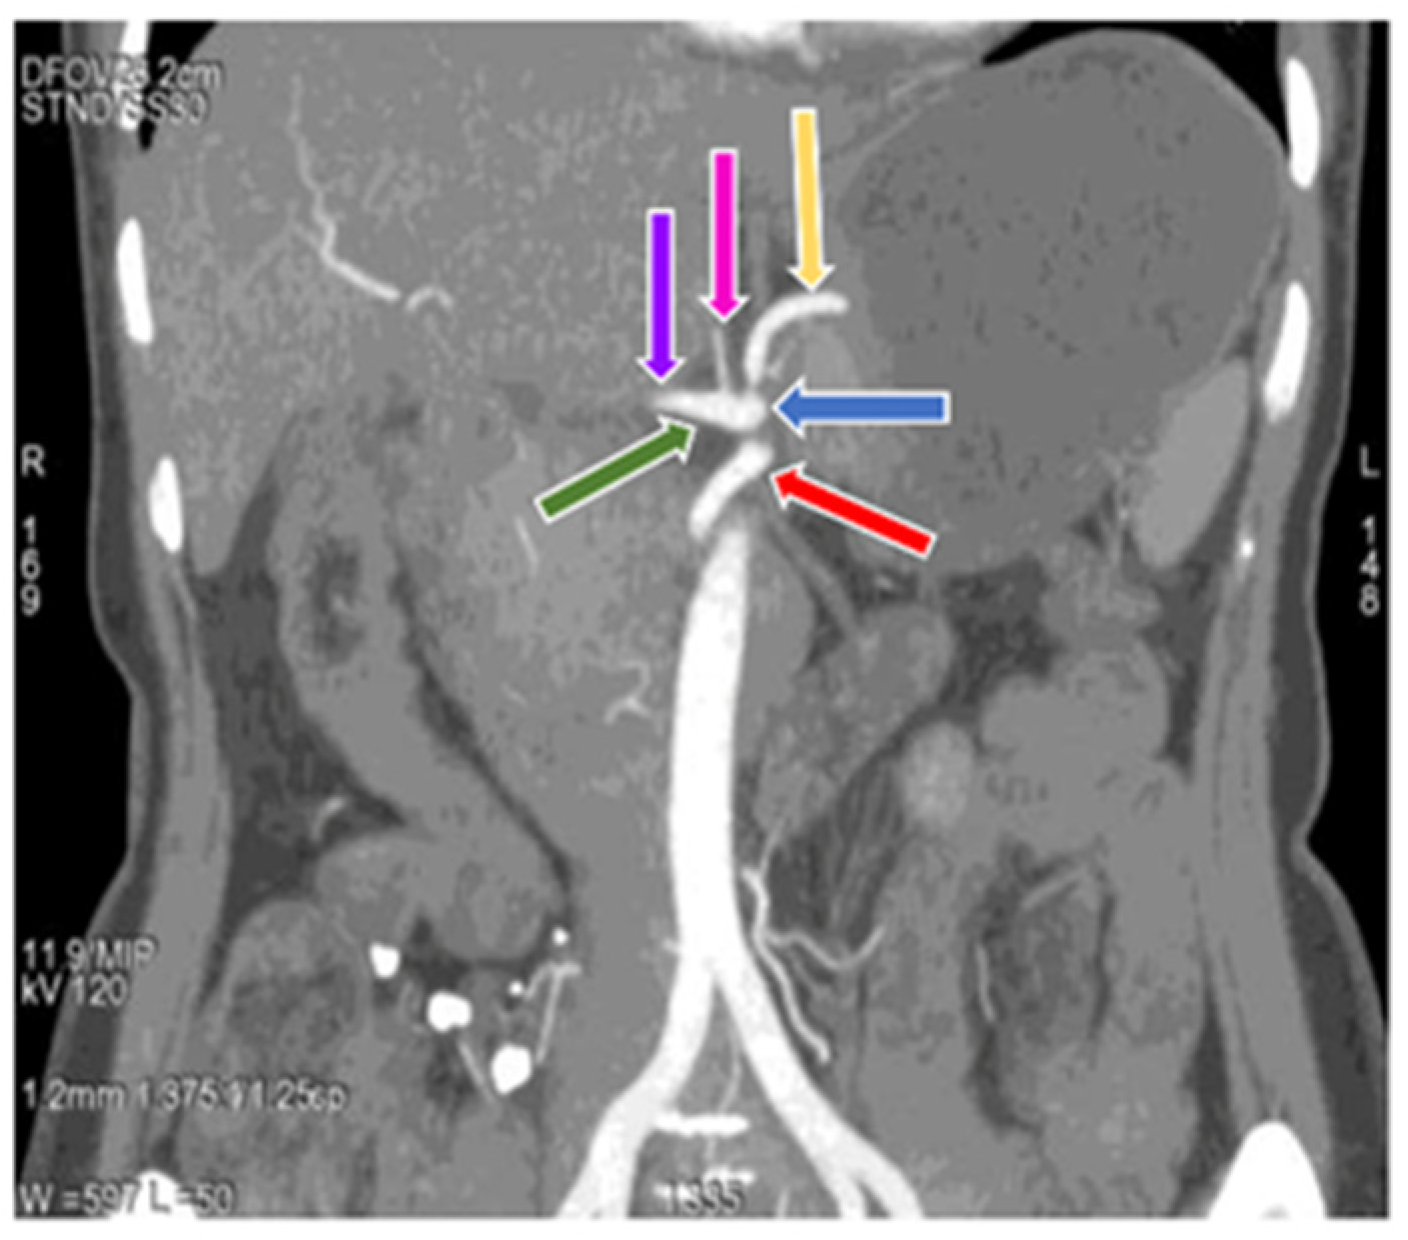

3.1. Variation in Origin and Branching Pattern of Celiac Trunk

3.2. Variation in Origin and Branching Pattern of Hepatic Artery